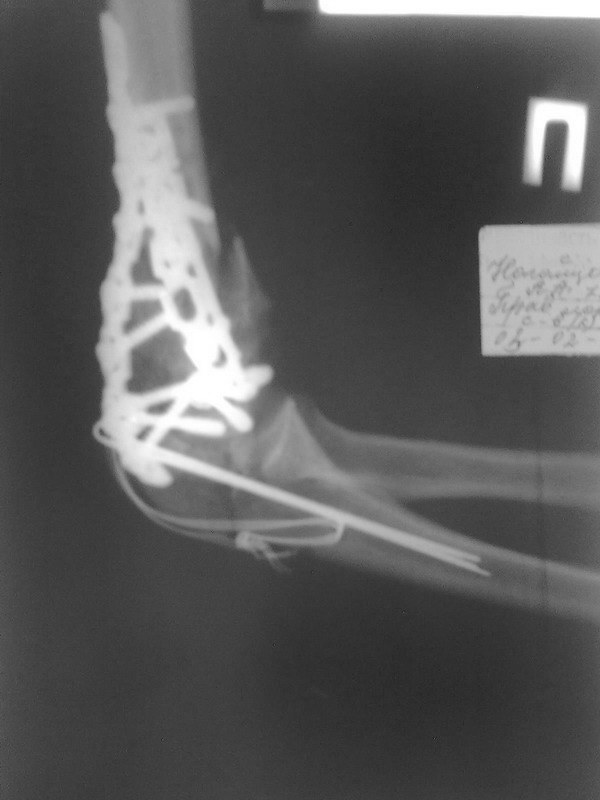

Уважаемые коллеги. Помогите советом определится с тактикой дальнейшего лечения. Пациентка, 16 лет. В 02.2011 - тяжелая сочетанная травма ОДА, груди, живота. В т.ч.открытый многооскольчатый чрезмыщелковй перелом правого плеча и локтевого отростка

Прооперирована на 2 сутки - остеосинтез реконструктивными пластинами плеча и локтевого отростка по типу Weber. В мае 2011 - явления спицевого остеомиелита на фоне слабой консолидации . Спицы удалены. Свищи закрылись. Больная ушла на реабилитацию в поликлинику.

На томографе от 09.2011 - вялая консолидация перелома плеча и локтевого отростка. на томографе от 02.2012 - картина схожая - вялоконсолидирующийся перелом правого плеча, вялоконсолидированный перелом локтевого отростка, угловая деформация по типу варусной. Контрактура локтевого сустава - сгибание 100, разгибание 80, супинация 45, пронация 40.

В наших планах выполнить костную пластику с удалением реконструктивных пластин и с установкой LCP пластин, есть ли смысл в остеотомии для коррекции варуса?. И будет ли смысл в этом. Хотелось бы увеличить амплитуду движений в суставе. Реально ли это на фоне такой картины?. Заранее спасибо